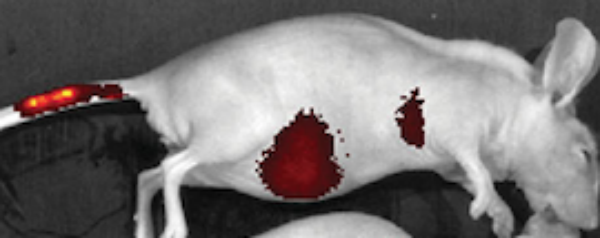

Voor het eerst is in muizen aangetoond dat ingespoten stamcellen naar een bepaalde plek kunnen worden gestuurd. Amerikaanse onderzoekers brachten ijzeroxide-nanodeeltjes in de cellen en labelden ze. Vervolgens spoten ze de cellen in muizen. De meeste cellen verplaatsten zich naar de staart, waar een magneet zat (linkermuis op de afbeelding hieronder). Zonder de magneet bleken de cellen vooral in de longen en lever terecht te komen (rechtermuis).